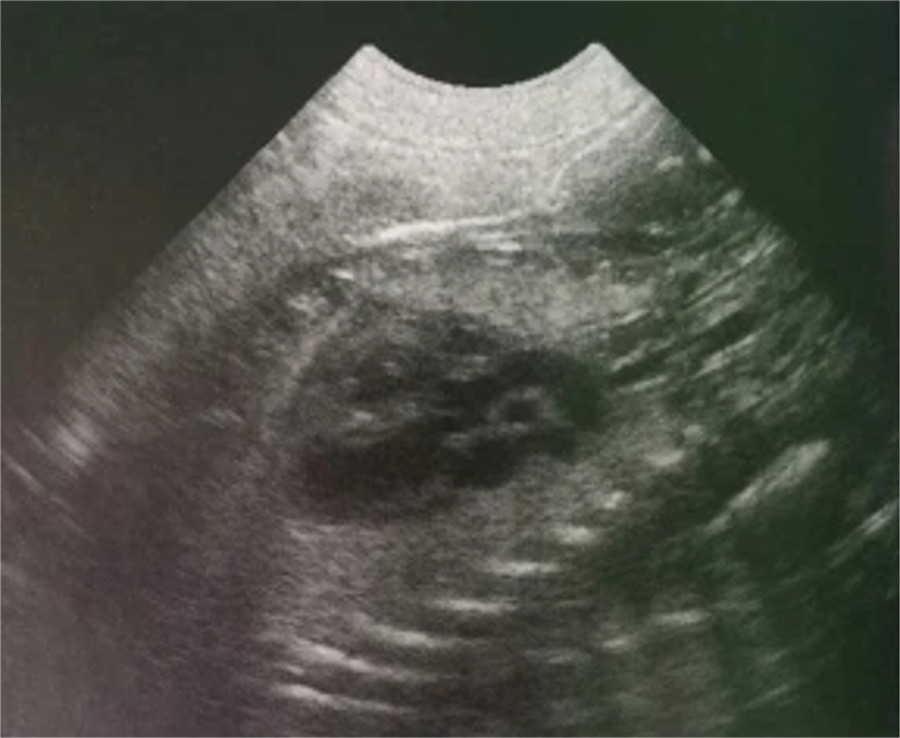

Aunque no es algo obligatorio es recomendable realizar alguna ecografía durante la gestación, siendo para ello un buen momento en torno al día 40, ya que en este momento los cachorros están prácticamente formados del todo pudiendo apreciarse el latido cardíaco (desde el día 23-25 después de la monta), el movimiento fetal (desde el día 35 de gestación), el esqueleto (desde el día 33-39 postmonta) e incluso el hígado y los pulmones.

Este medio diagnóstico nos permite además realizar una predicción bastante aproximada del momento del parto mediante la medición de diferentes perímetros fetales.